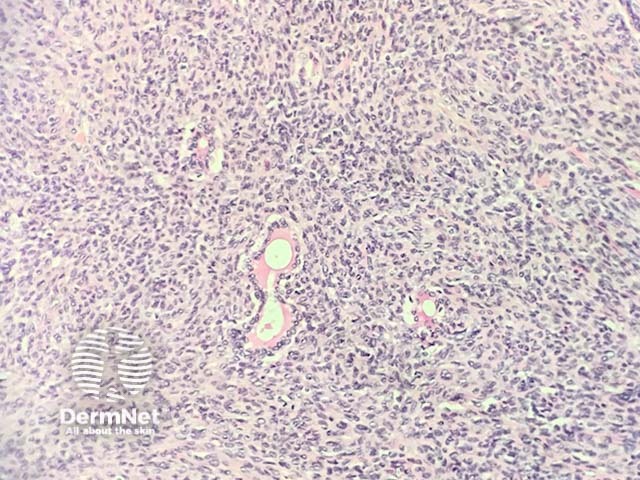

The histopathology in synovial sarcoma may be biphasic (consisting of spindled and epithelioid cells), monophasic (only spindled cells), or undifferentiated (difficult to recognise without cytogenetic tests). These tumours are usually present in the deep soft tissues but occasionally they are seen in the dermis (figure 1). The spindle cells are arranged in plump fascicles with hyalinization and distinct lobulation (figures 2,3) Biphasic tumours have spindle cells resembling synoviocytes and plump epithelial cells forming glands/cords (figure 4, the epithelioid component is indicated with the arrow).

Figure 2

Figure 3